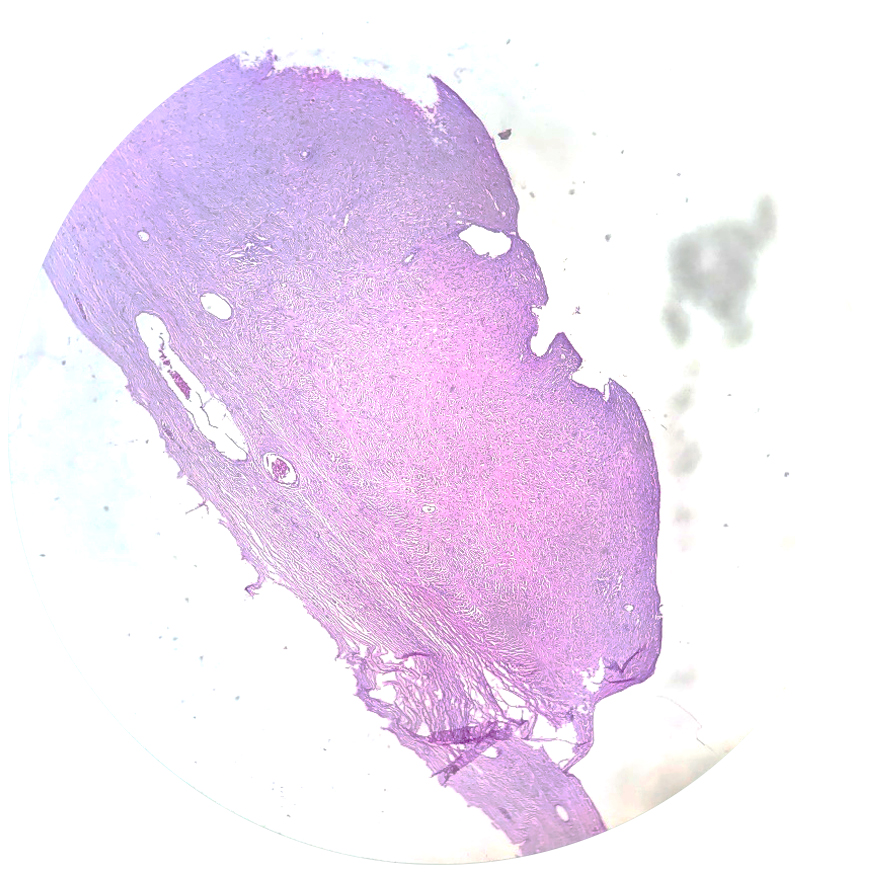

Las inclusiones benignas son focos de tejido ectópico (Tejido fuera de su lugar de origen) no neoplásico en los ganglios linfáticos. Ellos son clasificados en tres grupos: epitelial, nevomelanocítico y decidual.